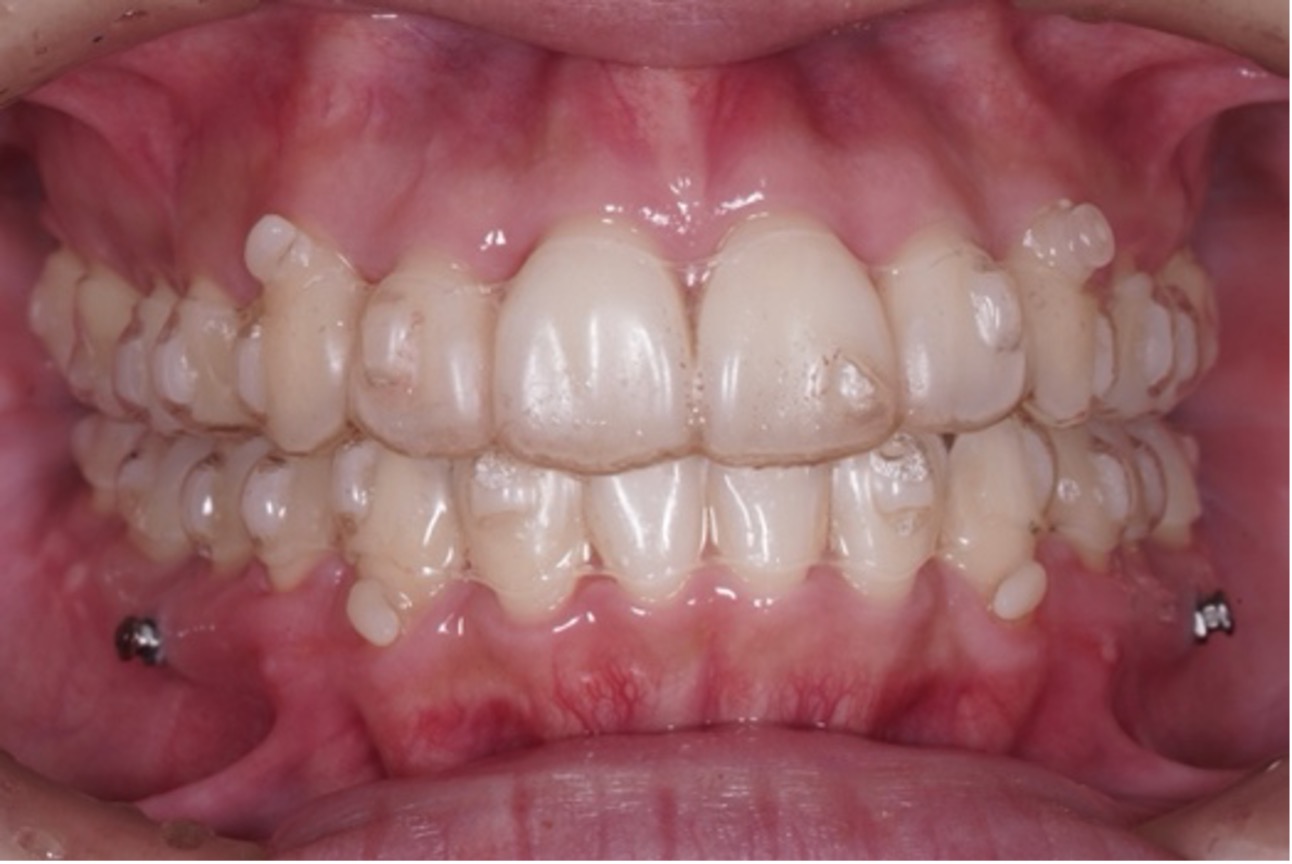

近年は、「ワイヤーで歯の土台を整え、マウスピースで最終調整を行う」ハイブリッド矯正が人気を集めています。

⚫︎見た目・精度・期間のバランスが良い

⚫︎症例に合わせて柔軟に対応可能

⚫︎治療期間の短縮が期待できる